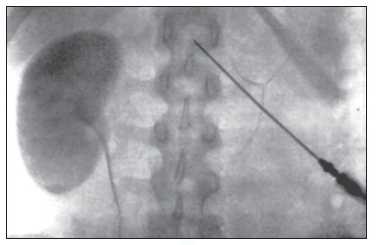

Аплазия левой почки

Удвоенная почка без признаков обструкции